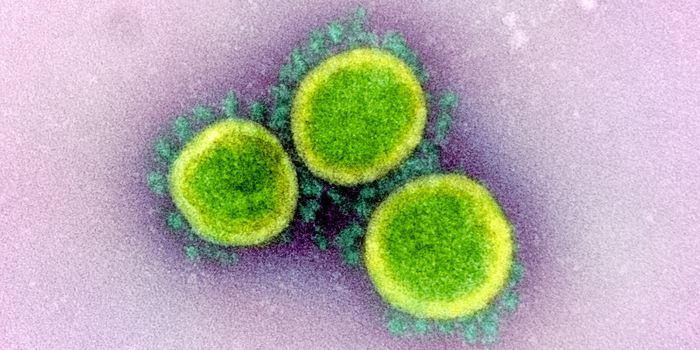

APR 27, 2020MicrobiologyThe pandemic virus that causes COVID-19 has now infected nearly 3 million people, and killed over 200,000.

MAY 10, 2021MicrobiologyThe pandemic virus SARS-CoV-2 has changed the world in devastating ways, taking hundreds of thousands of lives & new var ...

MAR 03, 2020MicrobiologyThere have now been nine deaths in the United States, all in Washington state from COVID-19, the illness caused by the n ...

MAR 10, 2020MicrobiologyThe vast majority (97.5%) of people will develop symptoms of infection within 11.5 days of exposure to the virus.

MAR 01, 2020MicrobiologyWorldwide, the number of COVID-19 cases, caused by the SARS-CoV-2 virus, is still rising.